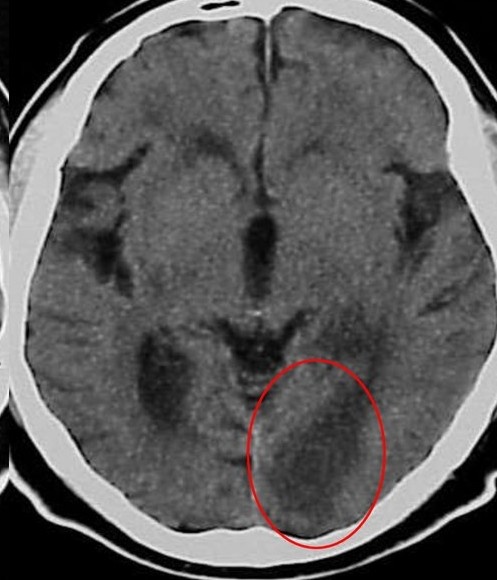

Симптом яркой СМА на аксиальном срезе КТ головного мозга, сглаженность субарахноидального пространства и нечеткость базальных ядер - вот, на что должен обратить внимание рентгенолог при КТ-исследовании пациента с неврологической симптоматикой.

- Зона пониженной плотности в веществе головного мозга. Обнаружение в первые 6 часов гиподенсной зоны является специфичным признаком необратимого ишемического повреждения мозга. У пациентов с клиникой инсульта и выявленной гиподенсной областью на КТ в первые 6 часов есть риск увеличения зоны ишемии. Кроме этого, у таких пациентов хуже ответ на проводимую медикаментозную терапию.Таким образом,выявление гиподенсной зоны является неблагоприятным прогнозом;

- Симптом плотной СМА или симптом точки (проявляется вследствие тромбоза СМА или значимого замедления кровотока по тому или иному сегменту артерии);

- Островковый ленточный симптом (включает в себя гиподенсную зону и отек коры головного мозга в области островка. Область головного мозга, кровоснабжаемая СМА, очень чувствительна к гипоксии в связи с тем, что СМА не имеет коллатералей).